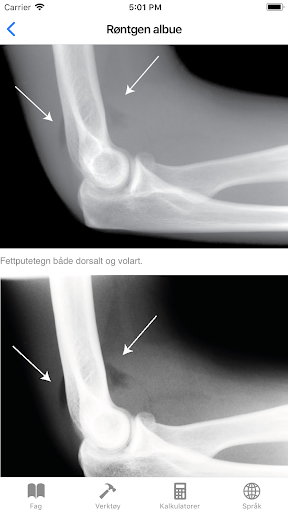

Łokieć rentgenowskie